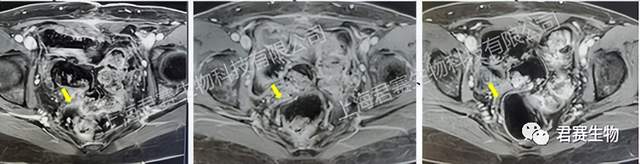

近日,君赛生物传来振奋人心的消息:其自主研发的肿瘤浸润淋巴细胞(TIL)产品GC101,成功帮助一位晚期子宫内膜癌患者达成完全缓解(CR),并保持无癌状态超过4年!这一突破性案例为难治性妇科肿瘤治疗开辟了新路径。

2021年3月,L女士在体检时发现异常:卵巢占位伴淋巴结肿大,肿瘤标志物CA125和CA199飙升至200U/mL以上。影像学检查高度怀疑子宫内膜癌伴淋巴结转移。之后发现肿瘤已扩散至大网膜和盆腔,多轮化疗与帕博利珠单抗联合仑伐替尼的治疗方案均无效。

2021年8月,L女士参与君赛生物GC101 TIL细胞临床试验。经过两个月的治疗后,奇迹开始显现:肿瘤标志物持续下降,肿瘤病灶不断缩小,治疗两个多月后各项指标已基本恢复正常。治疗当晚即感身体轻松,迎来“全新生活起点”,至今四年状态如常。

图片源于君赛生物

该案例表明TIL细胞疗法(GC101)在妇科肿瘤中具有有希望的效果。